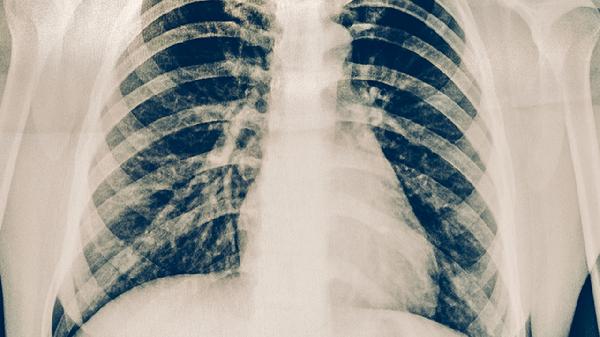

肋骨骨折并发开放性气胸时,由于胸腔与外界直接相通,负压环境被破坏,导致肺组织塌陷。患者会出现呼吸频率加快、呼吸深度变浅等表现,严重时可出现三凹征。此时需立即封闭伤口,保持患侧卧位,避免气体继续进入胸腔。

气体经胸壁伤口进入皮下组织,可触及捻发感。皮下气肿可能从胸部向颈部、面部扩散,导致局部肿胀。这种情况提示存在进行性气胸,需尽快行胸腔闭式引流术,临床常用一次性使用胸腔引流装置。